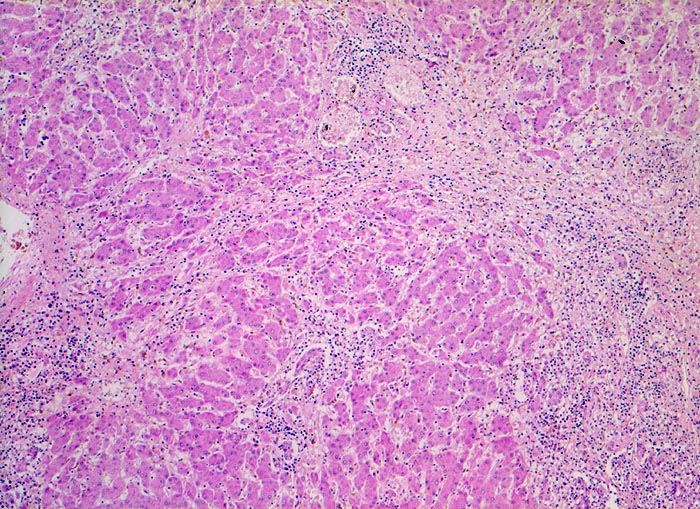

Das histologische Bild der akuten Hepatitis vom Virustyp ist gekennzeichnet durch eine lobuläre Entzündung bei fehlender portaler Fibrose und nur geringer entzündlicher Infiltration der Portalfelder. Es finden sich ballonierte Hepatozyten, Apoptosen (> 1164) und fleckige Nekrosen. Perivenuläre Nekrosen, Brückennekrosen oder konfluierende multilobuläre Nekrosen und eine läppchenzentrale Cholestase können vor allem in klinisch fulminant verlaufenden Fällen nachgewiesen werden. Zahlreiche Makrophagen, welche Diastase-PAS positives Zeroidpigment (> 4319) von phagozytierten nekrotischen Hepatozyten enthalten, zeugen im subakuten Stadium von einer abgelaufenen akuten Hepatitis mit Parenchymnekrosen. Eine Unterscheidung der verschiedenen Typen der viralen Hepatitis und einiger Formen medikamentöser Hepatitiden gelingt rein morphologisch aufgrund des unspezifischen Bildes meist nicht. Für eine ätiologische Klassifizierung sind zusätzliche klinische Angaben erforderlich (Anamnese, Medikamente, Serologie).

• Regelrechte Läppchenarchitektur.

• Lobuläre gemischte Entzündung.

• Ansammlungen zeroidbeladener Makrophagen innerhalb von Parenchymnekrosen (abgebaute fleckförmige Nekrose).

• Apoptosen (hypereosinophile abgerundete Leberzellen).

• Portale gemischte Entzündung.

• Fehlende Fibrose.